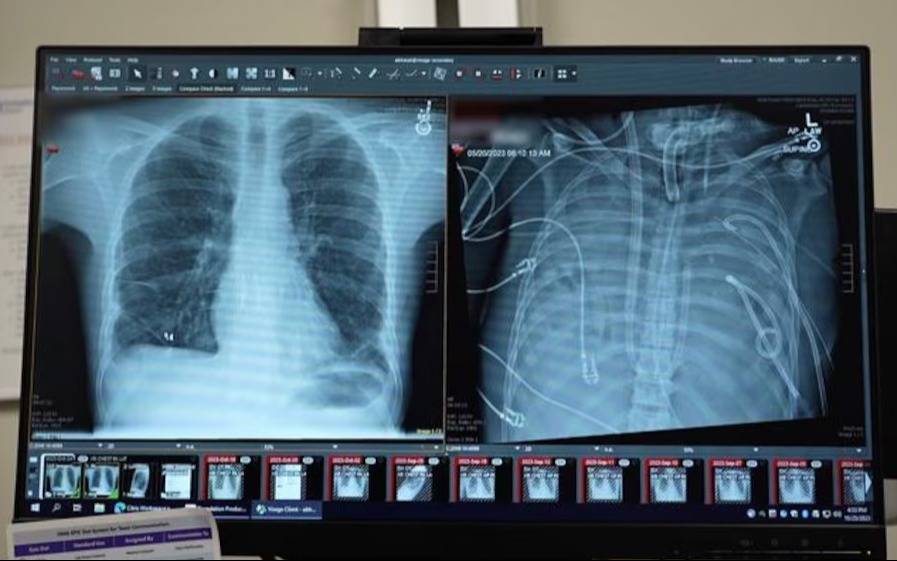

Los pulmones nuevos (izquierda) y los pulmones viejos (derecha) del paciente (Northwestern Medicine)

Un equipo médico de Estados Unidos logró mantener con vida durante 48 horas a un hombre de 33 años sin pulmones, mediante un sistema artificial desarrollado en el hospital Northwestern Memorial de Chicago. El paciente permaneció conectado al dispositivo hasta recibir un doble trasplante pulmonar. El procedimiento fue publicado en la revista científica Med y estuvo a cargo del cirujano torácico Ankit Bharat, de la Northwestern University Feinberg School of Medicine.

El hombre había ingresado al hospital con una infección por influenza B que derivó en una neumonía bacteriana grave. La evolución del cuadro provocó síndrome de dificultad respiratoria aguda, una condición en la que los pulmones dejan de cumplir su función de oxigenar la sangre. Posteriormente, una infección por Pseudomonas aeruginosa, una bacteria resistente a los antibióticos, agravó el estado general del paciente y derivó en fallas cardíacas y renales.

Según relataron los médicos, el paciente sufrió un paro cardíaco al momento de su ingreso y requirió maniobras de reanimación. Los pulmones presentaban un daño severo y sostenido, por lo que mantenerlos implicaba conservar el foco infeccioso. Dado que el estado clínico impedía realizar un trasplante inmediato, el equipo optó por extirpar ambos pulmones y utilizar un sistema de pulmón artificial total.

Tras la extracción de los pulmones infectados, los médicos observaron una estabilización de la presión arterial y una recuperación progresiva de la función de otros órganos. El paciente permaneció durante 48 horas sin pulmones naturales, bajo monitoreo constante y conectado al sistema artificial. Luego de confirmarse la mejoría clínica, fue incorporado a la lista de espera para trasplante pulmonar.

Dos días después, se realizó el trasplante doble de pulmón. De acuerdo con el seguimiento médico, más de dos años después de la intervención el paciente presenta una función pulmonar normal y no registra complicaciones asociadas al procedimiento.

El análisis de los pulmones extraídos mostró un daño irreversible del tejido, con cicatrices y destrucción a nivel molecular. Los investigadores indicaron que estos hallazgos aportan evidencia sobre la imposibilidad de recuperación en determinados casos de síndrome de dificultad respiratoria aguda.